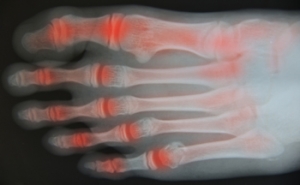

Foot arthritis causes inflammation and damage to the joints of the foot, leading to pain, stiffness, and reduced mobility. Osteoarthritis results from wear and tear of the joint cartilage over time. Rheumatoid arthritis is an autoimmune condition where the body attacks its own joints, causing swelling and deformity. Additionally, post-traumatic arthritis develops after an injury or fracture, while gout occurs when uric acid crystals accumulate in the joint, causing sudden and severe pain. A podiatrist can diagnose the specific type of arthritis, recommend treatments such as custom orthotics or medication, and provide guidance to improve mobility. If you have symptoms of arthritis in your feet, it is suggested that you are under the care of a podiatrist.

Arthritis is a term that is commonly used to describe joint pain. The condition itself can occur to anyone of any age, race, or gender, and there are over 100 types of it. Nevertheless, arthritis is more commonly found in women compared to men, and it is also more prevalent in those who are overweight. The causes of arthritis vary depending on which type of arthritis you have. Osteoarthritis for example, is often caused by injury, while rheumatoid arthritis is caused by a misdirected immune system.

During your lifetime, you will probably walk about 75,000 miles, which is quite a lot of stress to put on your feet. As you get older, the 26 bones and 30 joints in each of your feet will lose flexibility and elasticity. Your foot’s natural shock absorbers will wear down as well. Having arthritis added to this mix only makes matters worse. Your joints will become distorted and inflamed, which is why arthritic foot care needs to be something to think about every day.